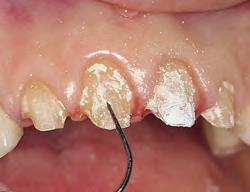

1. For restorations, Astingedent™ X hemostatic and Ultrapak cord are ideal for controlling blood and sulcular fluids and can also protect tissue from burs. Use a firm air/water spray to remove excess hemostatic solution.

1. Packing Ultrapak cord quickly displaces tissues and improves access for indirect veneer luting.

FOR IMPRESSION TAKING

An astringent is a substance that eliminates permeability of epithelium to tissue fluid flow. The result is a dry field, an important tissue management solution. An ideal impression for successful crowns, veneers, and bridges must accurately capture the preparation margins. This can be ensured only through reliable hemostasis and gingival displacement.

1. Subgingival preparation with bleeding. BLEEDING HEMOSTASIS